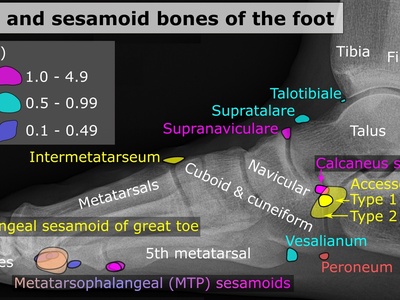

| Os peroneum | Within peroneus longus tendon near the cuboid at the lateral midfoot | Reduces friction and transmits peroneus longus tendon force across cuboid | Variable (5-26%) | Lateral foot pain, peroneus longus tendinopathy, fracture |

Os peroneum

The os peroneum is a sesamoid inside the peroneus longus tendon near the cuboid bone. It helps tendon leverage and smooths tendon passage under the foot. It can fracture or cause lateral foot pain and is associated with peroneus longus tendinopathy.

Lesser toe sesamoids (MTP II–V)

Some people have small sesamoids under the MTP joints of toes two through five embedded in flexor tendons or plantar plates. They’re variable and often asymptomatic but can contribute to forefoot pain, bursitis, or be mistaken for accessory ossicles on imaging.